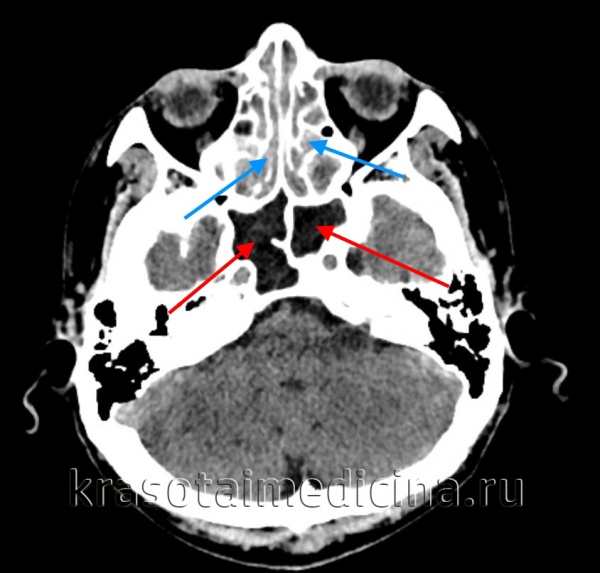

КТ ППН. Полипозный пансинусит. Отек слизистой оболочки верхнечелюстных пазух (красная стрелка), полиповидные образования в в/челюстных пазухах (синяя стрелка), выраженное снижение пневматизации полости носа (зеленая стрелка).

КТ ППН. Этот же пациент. Диффузное снижение пневматизации ячеек решетчатого лабиринта (синяя стрелка), гиподенсный отек слизистой оболочки сфеноидальных пазух (красная стрелка).